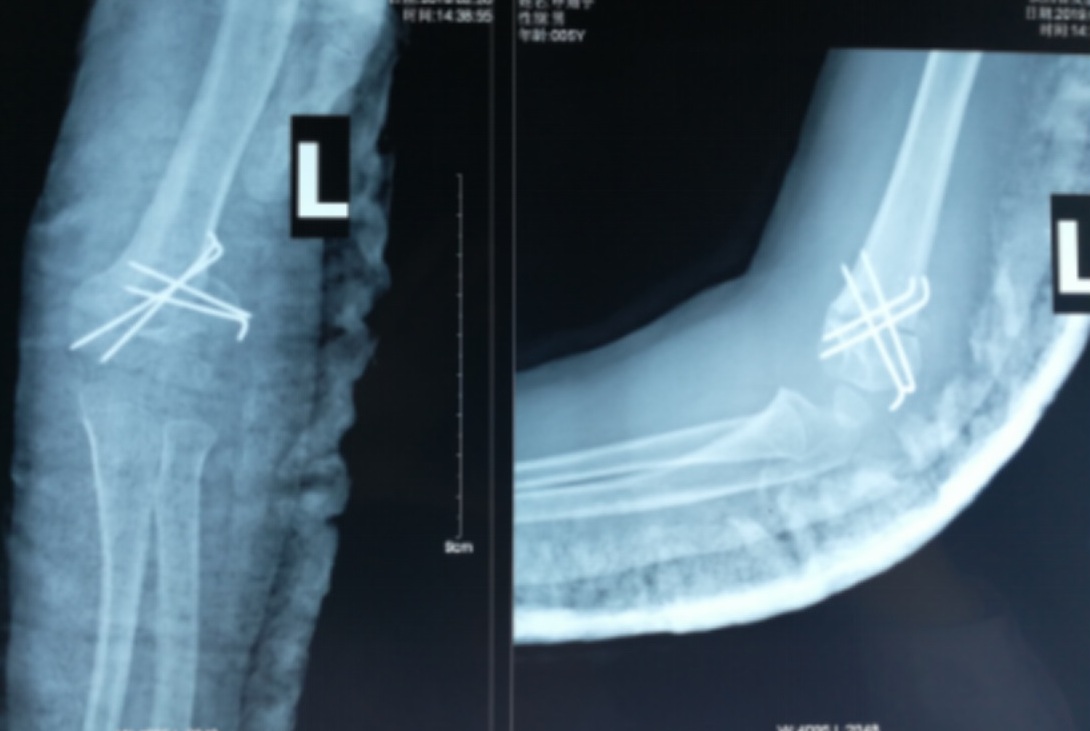

手术指征:肘内翻畸形外观失常,同时影响患肢发育和功能。据国内文献报道,大部分患者为内翻角超过10°。肘内翻畸形很难自我重塑,即自然矫正的可能性甚微,不仅影响美观,还存在一些晚期并发症,如慢性疼痛、尺神经麻痹、后外侧旋转不 稳定、肘关节弹响、增加外髁和其他继发性骨折的风险等。大部分手术指征为整形,在没有功能问题的情况下患儿的家长对孩子手臂的外观不满意,要求治疗。另外从社会意义上出发,肘内翻畸形可能会影响儿童的心理健康。因此,目前建议一旦确诊肘内翻,应选择合适时机进行手术矫正治疗。

手术时机:骨折骨性愈合、畸形发生后的随访过程中肘内翻未继续进展即可尽早手术。患儿年龄越小,骨骼韧性越高,截骨时保留的骨皮质铰链不易断裂,术后位置维持也更稳定。因此,我们认为:骨折已骨性愈合,肘关节功能良好,但双上肢明显不对称、测量肘内翻超过10度,此时要考虑手术纠正。